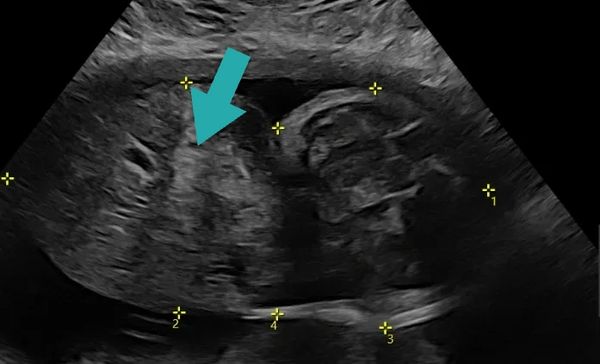

(Pic: fetal ultrasound with arrow demonstrating a giant omphalocele)

An omphalocele is a condition where a baby is born with some of their abdominal organs (like intestines or liver) sticking out through the belly button, covered by a thin clear sac. It happens very early in pregnancy when the belly wall doesn’t fully close